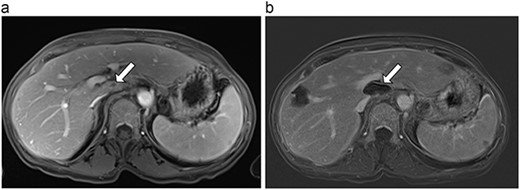

(a) Pre-ablation MRI demonstrates 6 mm lesion in caudate lobe of liver. (b) Post-ablation MRI (18 days postoperatively) demonstrates 40.4 mm complete ablation site in caudate lobe of liver.

| 1 (3a,b) | 61, F | Colon adenocarcinoma | 6-month FOLFOX | 1 | Laparoscopic microwave ablation | 6 | 40.4 | 34.4 | 10 | No |